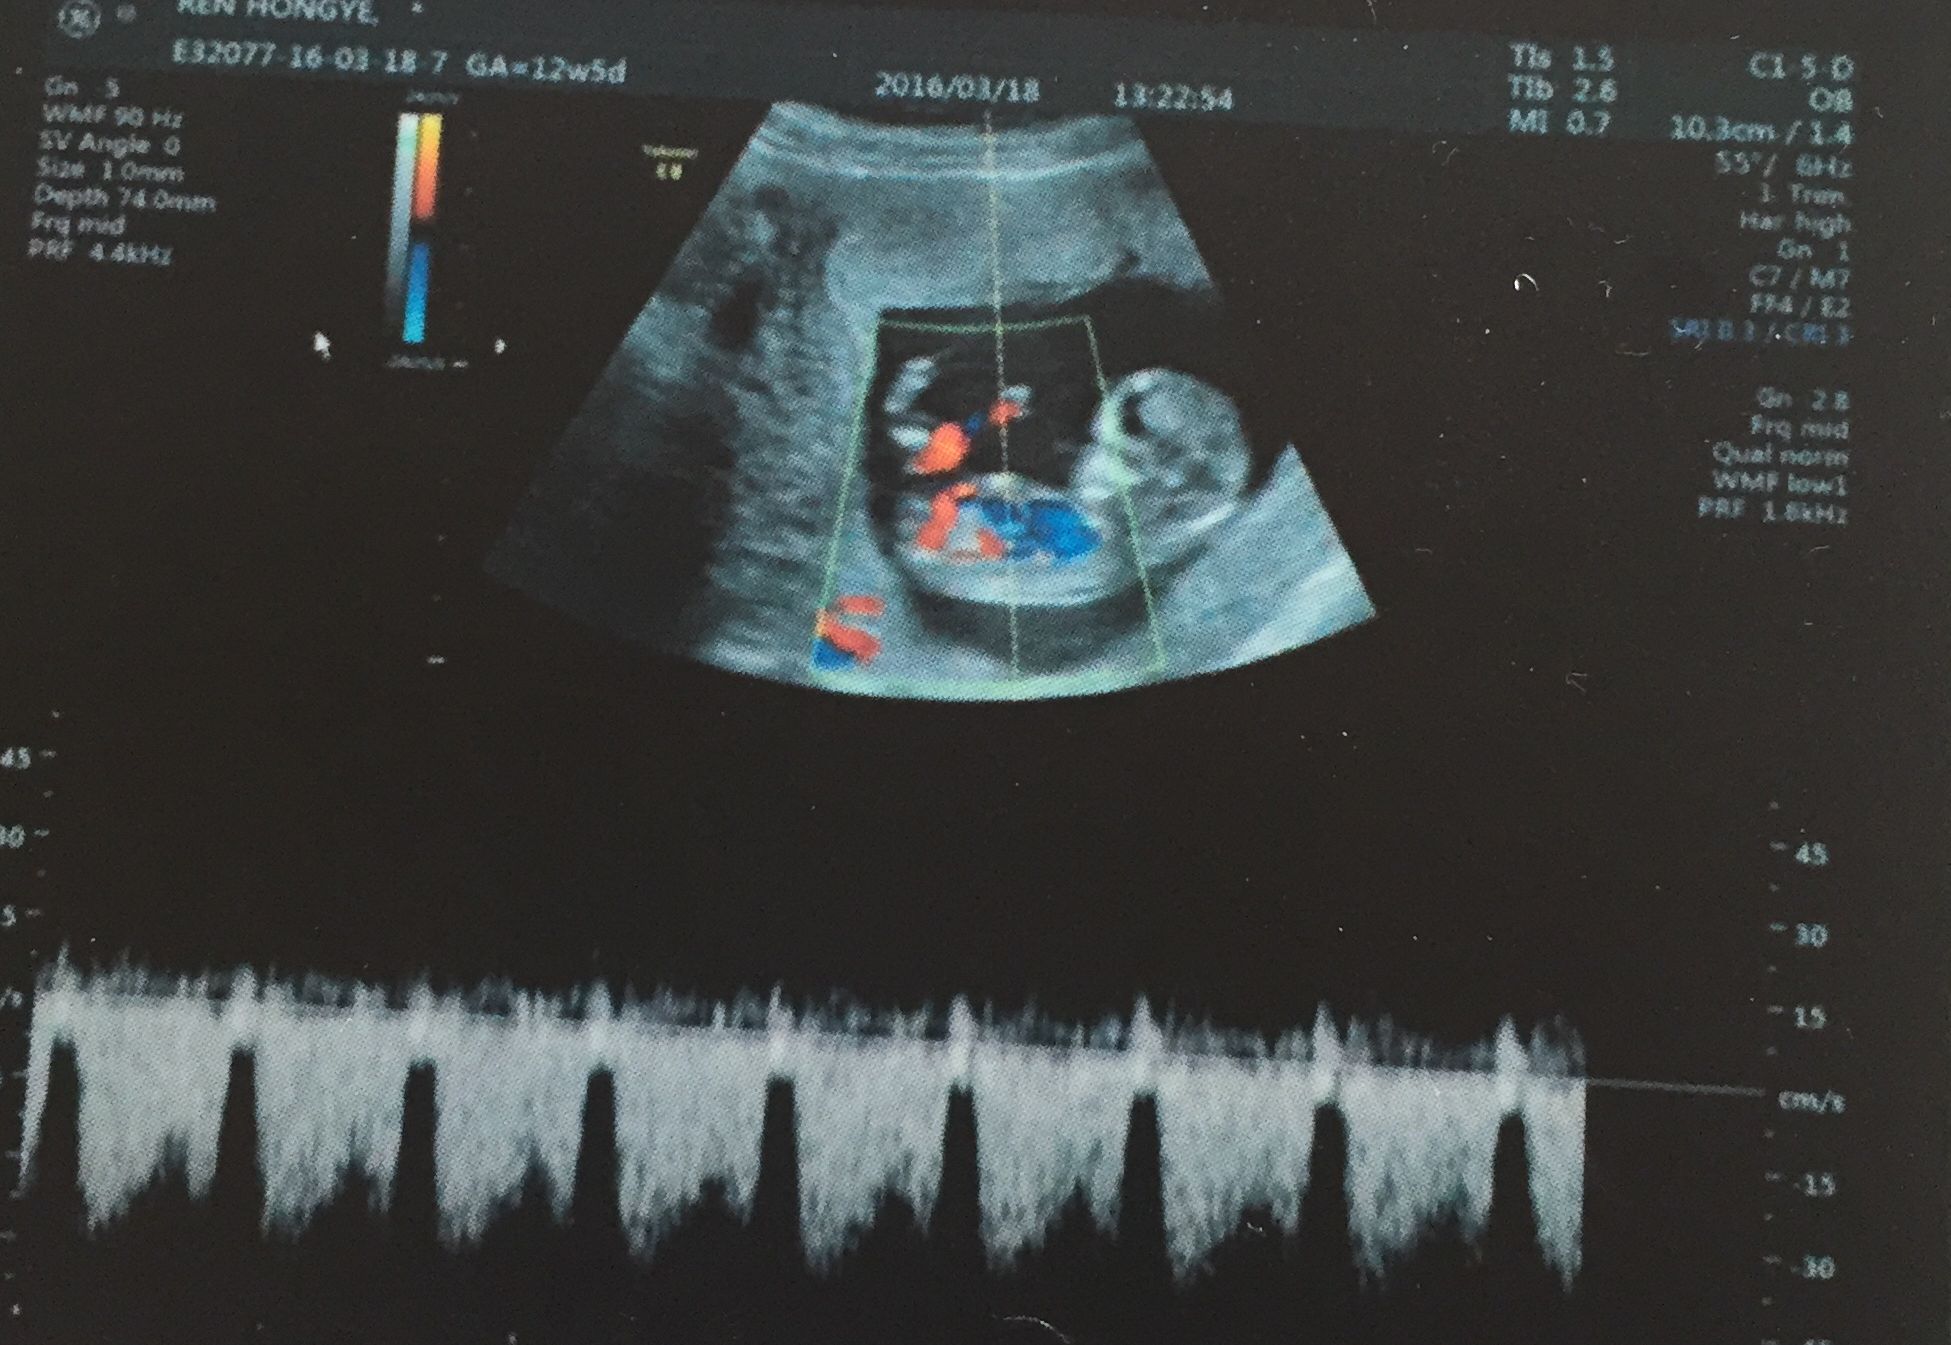

此时的淘淘还在我的肚子里,这是我在孕3个月时他的样子,这时候他身长约9cm,体重约14g